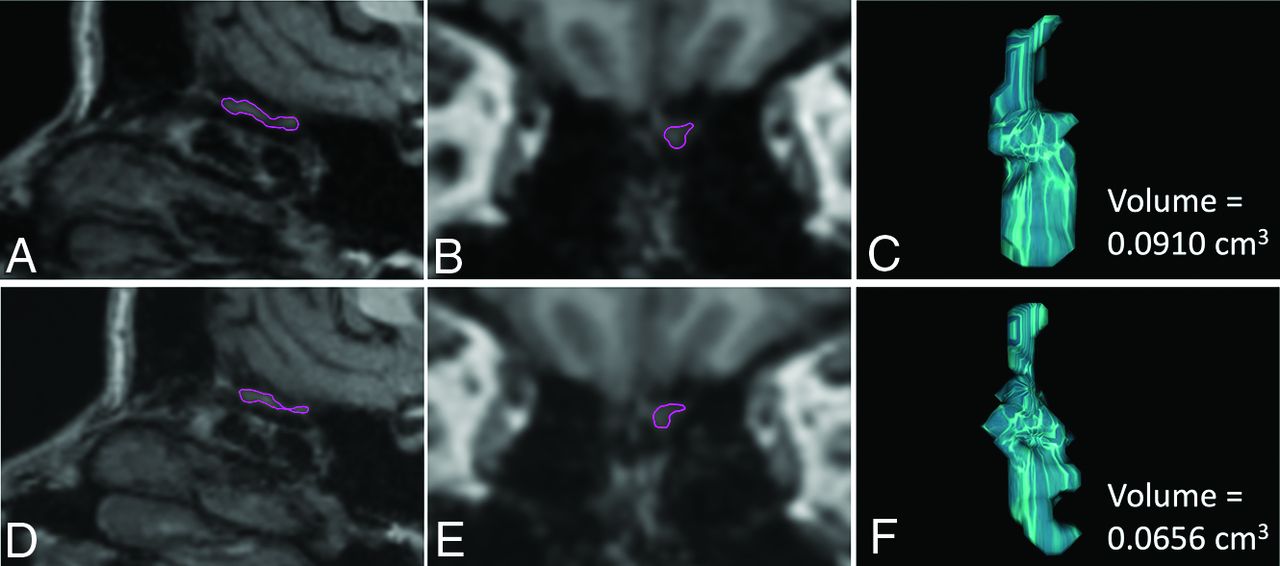

OB volume was assessed manually for each structural image and hemisphere (Fig 1). Data from both sessions for each participant were assigned to 1 of 2 experienced neuroradiologist raters (coauthors V.L. and M.B.) who were naïve to whether participants belonged to the C19+ or C19− groups. For the full cerebral cortex, voxel-based morphometry analysis was performed using the longitudinal pipeline in the Computational Anatomy Toolbox, Version 12.8 for SPM12 (http://www.fil.ion.ucl.ac.uk/spm/software/spm12). Our preregistered analysis plan was based on a cross-sectional publication,18 whereas the current study has a longitudinal nature. Consequently, we used the longitudinal pipeline in the CAT12 toolbox,19 which entails additional intrasubject processing steps and the use of Geodesic Shooting20 instead of the Diffeomorphic Anatomical Registration Through Exponentiated Lie Algebra Toolbox (DARTEL, part of SPM) for spatial registration.

Illustration of the volumetric measurements of the left OB in a C19+ participant, in whom a decrease in OB volumes was observed 11 months after infection compared with the premeasure. The upper panel shows sagittal (A) and coronal (B) reconstructions of the high-resolution 3D T1WI sequence from the premeasure MR imaging with the left OB delineated in purple and the resulting computed OB volume (C). The corresponding data are shown for the postmeasure in the lower panel (D–F).